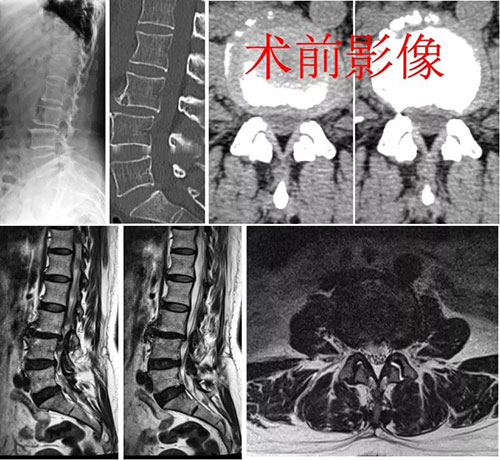

患者因腰痛加重伴右下肢疼痛、麻木半年前来医院就诊。接诊医师详细询问病史发现,患者1年半前就出现了腰部疼痛,久坐、久站后症状加重,休息可缓解。半年前上述症状加重,同时伴有右小腿后外侧疼痛麻木,腰前屈时症状缓解,后伸时症状加重,明显影响患者的生活和工作。

经检查,患者腰3椎体后滑脱,腰3/4节段明显不稳,腰椎CT和MRI检查显示L3/4椎管侧隐窝狭窄,右侧为重。以往此类合并腰椎不稳、腰椎滑脱需行腰椎融合手术的患者,需要经开放切口或管道撑开系统,剥离或劈开椎旁肌,才能完成神经减压、融合器置入、植骨融合等操作。